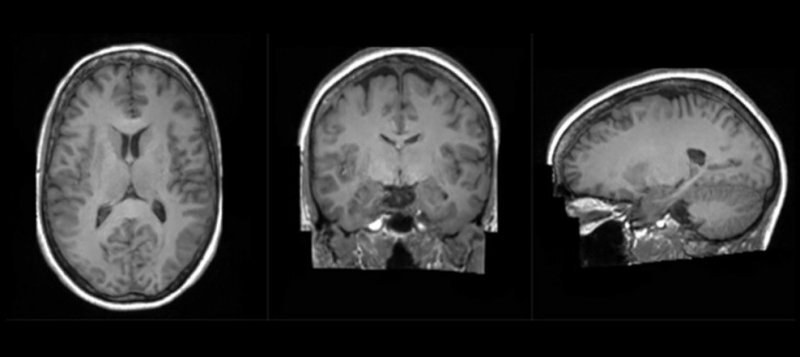

Сейчас суперкомпьютер используется для создания ИИ-моделей, способных генерировать синтетические изображения мозга на основе изображений, полученных с помощью МРТ. Это даёт возможность научить ИИ отличать здоровый мозг от больного, поскольку его тренируют на снимках пациентов разного возраста и с различными недугами. Как ожидается, в перспективе это позволит диагностировать возможные неврологические отклонения или заболевания мозга на ранней стадии.

Также новая методика с использованием ИИ может стать новаторским решением в понимании того, как формируется мозг, как травмы и болезни влияют на него, и как помочь ему восстановиться. Как отмечается, суперкомпьютер ускорил работы, сократив время обучение ИИ-моделей с месяцев до недель, а также дал возможность создавать более чёткие изображения.